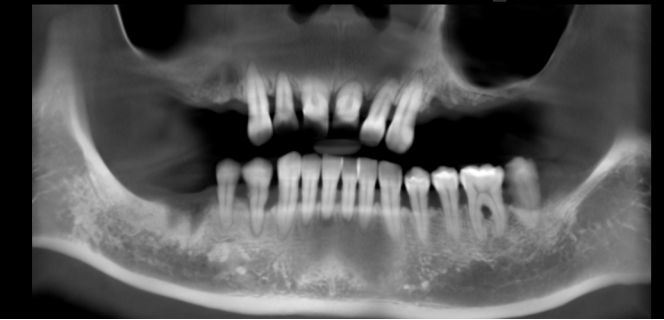

梁女士(化名),今年46岁,因早些年用牙习惯不好,导致牙齿问题比较多,比如前牙不好看,上面大牙所剩无几,余下几颗牙齿咀嚼无力,吃饭也不得劲,这让她很苦恼。

(梁女士术前牙片照)

后经朋友推荐,慕名找到我院种植技术院长钟春根主任,在经过全面诊疗与评估后,考虑到梁女士对形象美观有要求,加上她的牙槽骨条件还好,钟医生建议她做即刻负重种植,这样既能减少痛苦,又缩短诊疗时间,还能不影响形象美观。

经过充分的术前检查和准备,6月27日,钟主任为梁女士实施了半口即刻种植即刻修复手术。术中,钟主任采用微创拔牙方式,为她拔除了上颌残牙,并保存了拔牙创骨壁及牙槽间隔的完整性,随后立即为梁女士实施即刻种植手术,术中植入6枚种植体。1个小时后,手术顺利结束。之后经过一系列取模、咬颌重建,现场制作临时义齿,当天下午,梁女士就顺利戴上了临时假牙,也成为我院又一例半口即拔即种即刻修复的患者。